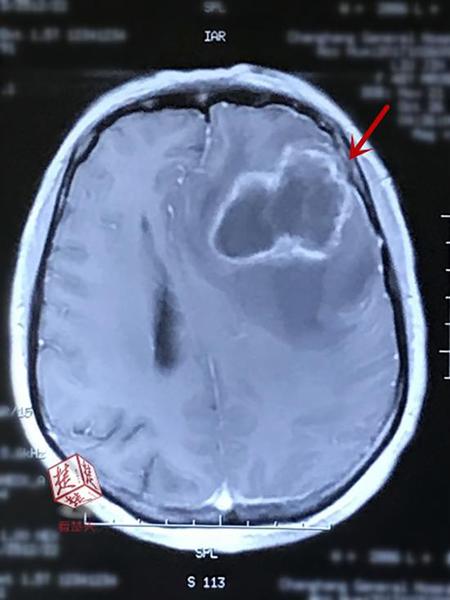

女子收养流浪猫狗感染细菌 引脑脓肿抽60毫升脓液

楚天都市报消息,爱心女子收养流浪猫狗,却意外感染细菌,脑里长脓包。近日,医生从孙女士的左脑里抽出60余毫升黄白色脓液。

经急诊检查,该院神经外科专家王焕明发现,孙女士的病灶是化脓性细菌感染引起的脑脓肿,可能由于其长期亲密接触猫狗,造成身体其他部位感染细菌,引发低烧,细菌栓子又从动脉血流播散到脑内,引起脑内发炎、化脓。由于未及时治疗且反复接触感染源,孙女士的脓包已扩大了7倍,并压迫脑神经频繁异常放电,影响右侧手脚活动及语言功能,必须手术予以清除。

11月6日,在神经导航下,王焕明精准定位脓肿,仅开了一个小孔植入导管,便将孙女士脑内的黄白色的脓液排除,抽吸了满满三个注射器,约60余毫升。术后,她还需接受至少一个月的消炎治疗,才能让脓壁闭合吸收。